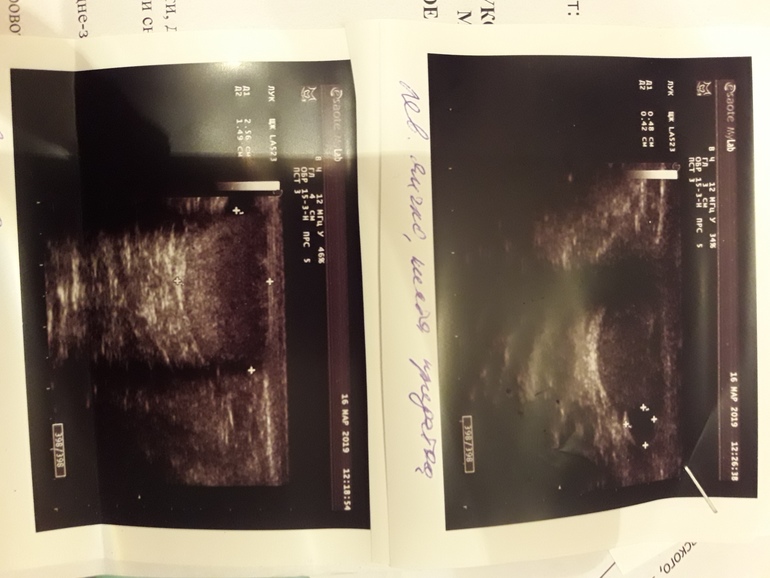

Здравствуйте.сделали узи мошенки мальчику 12 лет.показало диффузные изменения паренхимы яичек.фото прикрепляю(делали 2раза,в разных медцентрах).Подскажите,что это значит.опасаюсь самого страшного.К детскому хирургу попадем только через 3 дня,к андрологу через 4.помогите хоть немного прояснить ситуацию.(изначально обратились к урологу с проблемой задержка мочейспускания-чтобы помочиться ждет некоторое время...)спасибо.